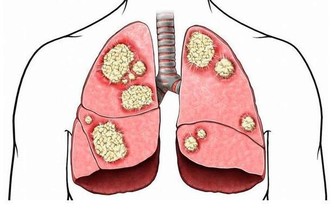

即使近年來醫療技術突飛猛進,可當癌細胞從前列腺擴散到身體其他部位時,也無法治愈這種疾病。